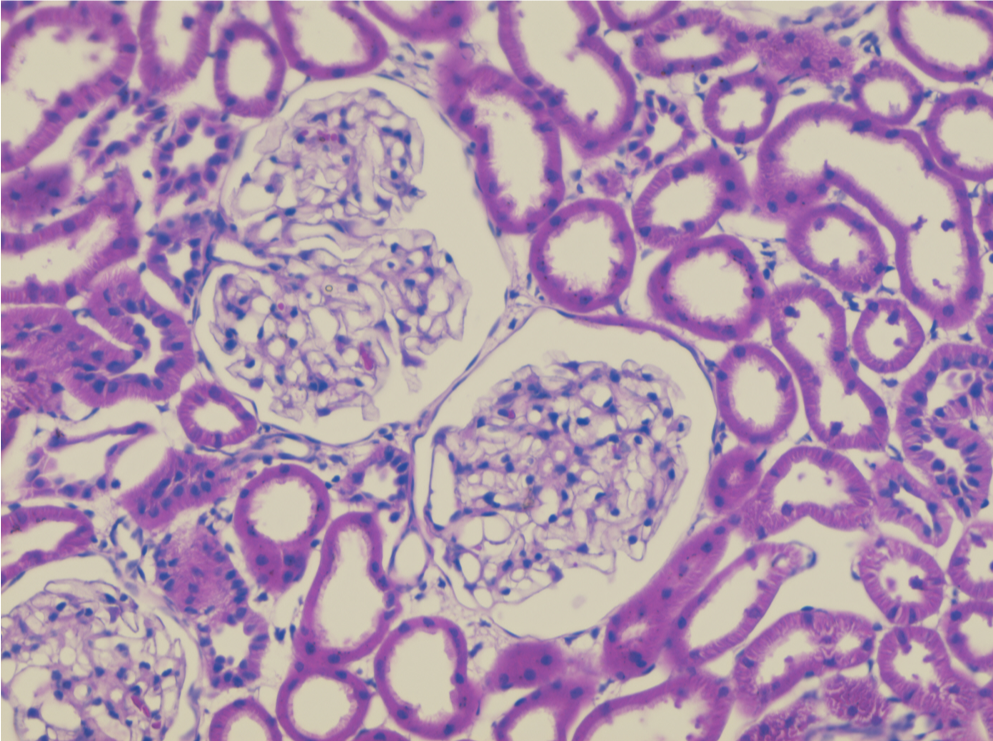

Histology also known as microscopic anatomy or microanatomy, is the branch of biology which studies the microscopic anatomy of biological tissues. Histology is the microscopic counterpart to gross anatomy, which looks at larger structures visible without a microscope.

At HistoScope we make histology slides and slide kits for the biotechnology/biology classroom. HistoScope offers Merritt histotechnology students an opportunity to experience real world histotechnician experience in a professional setting. HistoScope interns create high-quality H&E stained slides and perform quality control. Together, through sales and marketing, we work to promote and sell kits to the Bay Area Biosciences Education Community (BABEC).